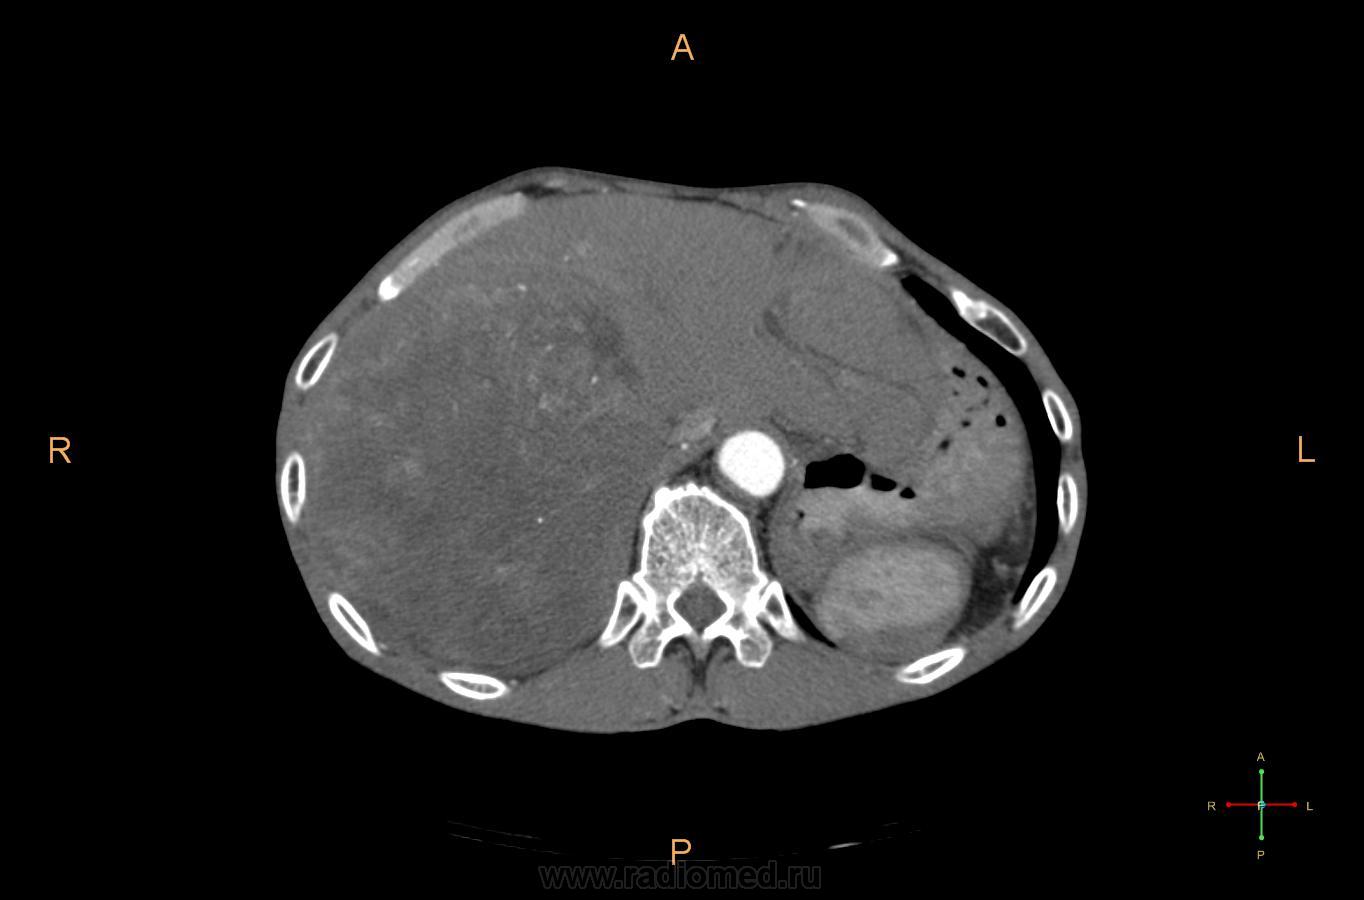

Пол пациента: Мужской пол Тип патологии: Злокачественное новообразование Область исследования: Пищеварительная система Методы исследования: КТ Пациент 64 лет с Ds: Хронический холангит в стадии обострения? ID:5078 Чт, 29/07/2010 - 16:29 #1 koriatus Не на сайте Был на сайте: 2 года 12 месяцев назад Зарегистрирован: 14.06.2010 - 01:49 Публикации: 452 Я бы думал о гепатоцеллюлярном раке. Чт, 29/07/2010 - 16:44 #2 rentgengb1 Не на сайте Был на сайте: 11 лет 11 месяцев назад Зарегистрирован: 13.02.2009 - 23:02 Публикации: 290 Согласен с Кориатус, гетерогенное контрастирование всего объема массы, в артериальную фазу прежде всего характерно для ГЦР. Чт, 29/07/2010 - 16:55 #3 v1tal Не на сайте Был на сайте: 4 года 9 месяцев назад Зарегистрирован: 07.06.2008 - 19:41 Публикации: 1779 Согласен с Вами, я тоже в заключении это указал, но от верификации пациент отказался, ему будет проводиться симптоматическая терапия. "Знаешь, у некоторых врачей есть комплекс мессии — им необходимо спасать мир. А у тебя комплекс Рубика — тебе необходимо решать головоломки."

Я бы думал о гепатоцеллюлярном раке.

Согласен с Кориатус, гетерогенное контрастирование всего объема массы, в артериальную фазу прежде всего характерно для ГЦР.

Согласен с Вами, я тоже в заключении это указал, но от верификации пациент отказался, ему будет проводиться симптоматическая терапия.